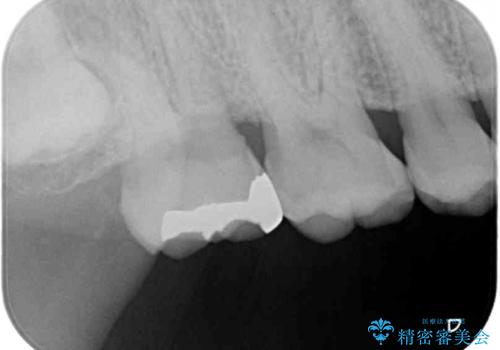

- 近医にて、銀歯の周りの歯が欠けてむし歯のようになっていると言われたとのことで来院された患者様です。

非常に咬合力が強く、銀歯やセラミックのような堅い素材では歯にダメージがかかり、治療を繰り返す可能性が高いと思われたので、ゴールドインレー(白金加金インレー、PGAインレー)にて、治療中の歯と銀歯が装着されている歯を修復治療することとしました。